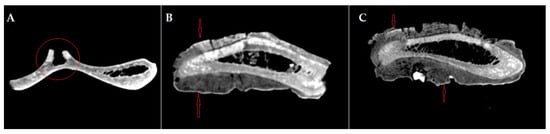

The gross features (Figure 1) detected in the distal portion of the scapula (neck of the scapula) include a major hypertrophy of the region due to the formation of an exuberant osseous tissue.

The newly formed bone tissue displays an irregular surface just dorsally (2–3 mm) to the glenoid cavity (Figure 1), all around the neck of the scapula. Consequently, the infraglenoid tubercle and the coracoid process are barely visible, being embedded in the osteophytes/exostoses situated in the neck of the scapula. The osteophytes and exostoses are most likely of cancellous bone, a fact suggested by the X-ray images (Figure 2).

Figure 3. CT images of the scapula: (A) axial section of the scapula, preserving the base of the dorsal spine on the cranial edge—red circle; (B,C) axial section of the scapula in the neck region of the scapula, intercepting the proliferated bone on both sides, lateral and medial—red arrows.